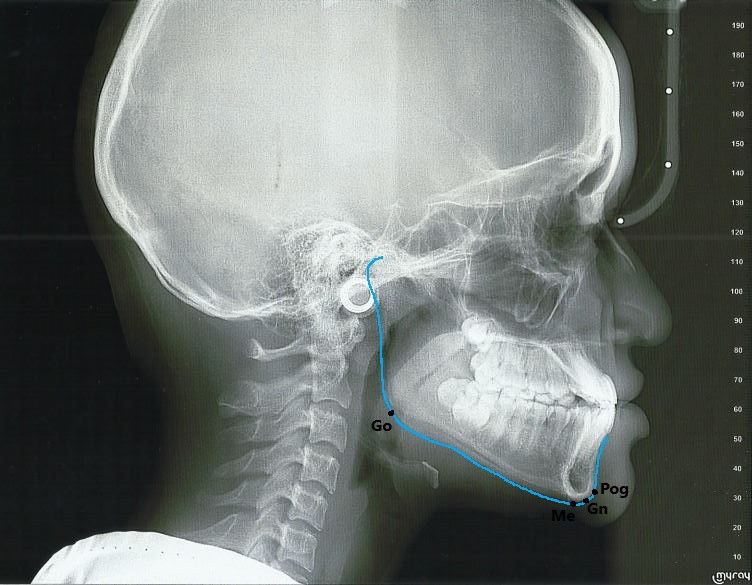

The location and function of the mandible is important for proper orthodontic treatment. The mandibular plane represents the lowest horizontal plane on a patient’s face. It is usually plotted by connecting anterior and posterior skeletal landmarks. On the lateral cephalogram it may be constructed using either of these landmarks: (1) Gonion-Menton, (2) Gonion-Gnathion or (3) tangent points on the inferior border of the mandible. The mandibular plane is usually related to the maxillary plane, either the sella-nasion (SN) plane or the Frankfort Horizontal plane, forming an angle which is significantly used for vertical dimension evaluation of the face. The following table shows the different landmarks used by various cephalometric analyses for the mandibular plane.

The sample radiograph shows the following landmarks. Gonion (Go) is the most posterior, inferior point on the mandibular angle. Gnathion(Gn) is the most anterior, inferior point on the mandibular symphysis. Menton (Me) is the most inferior point on the mandibular symphysis. Pogonion (Pog) is the most anterior point on the mandibular symphysis.